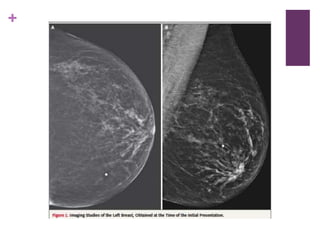

 3 días despues, se le realizaron una mastografía digital combinada

con tomosíntesis las cuales fueron negativas, sin sospecha de masas,

distorción de la arquitectura o microcalcificaciones.

 El US mamario orientado hacia las 10’ en la mama izquierda reveló

una masa superficial, oval e hiperecoica, de 6mm de diámetro en su

dimension mayor, con márgenes circunscritos localizados 5 cms del

pezón, en la dermis.

 El diagnóstico diferencial radiológico incluyó un quiste sebáceo, y la

masa fue diagnosticada inicialmente como benigna. Se citó 6 meses

después para seguimiento.